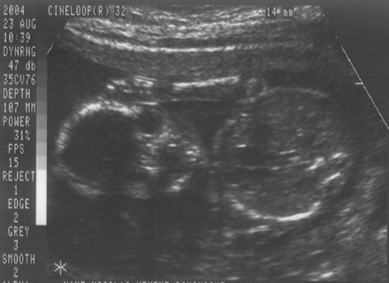

23. August 2004 (Ein Mädchen !)